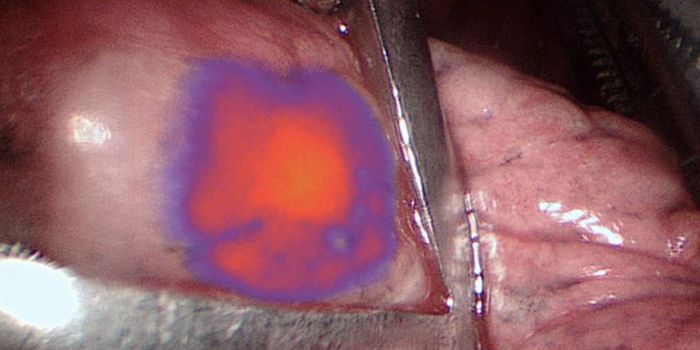

JUL 31, 2017

Cell & Molecular Biology

Scientists have found a way to highlight tumor tissue so it can be more effectively identified and removed.